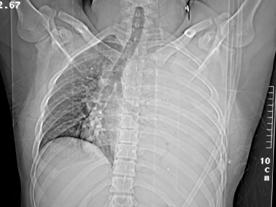

Hemo-pneumotorace stangDetaliu Fracturi costale multiple.Volet costal drept

Fracturi costale multiple Hemitorace drept strivit

Volet costal si hemotorace

drept Fracturi costale multiple

Volet costal si hemotorace drept

Hemitorace drept strivit Hemitorace drept strivit Hemitorace drept strivit